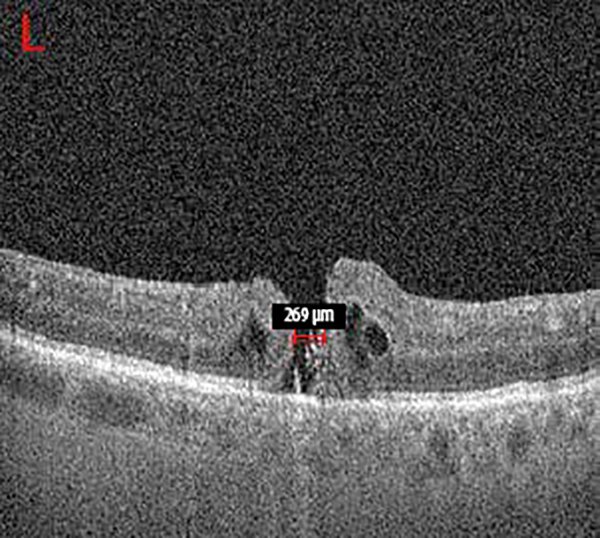

A los 21 días posfacoemulsificacion con extracción de AS en OI, concurrió por disminución visual nuevamente en su OI. Al examen con OCT se observó reapertura del AM en OI, esta vez con un diámetro de 269 micras y quistes intrarretinales ubicados en los bordes de dicha lesión (fig. 4).

Figura 4. Agujero macular en OI con un tamaño de 269 micras mediante OCT.

Se realizó VPP calibre 25 G, masajes sobre bordes del AM y posterior colocación de AS. Controles posquirúrgicos en parámetros conservados con AM cerrado en la primera semana.